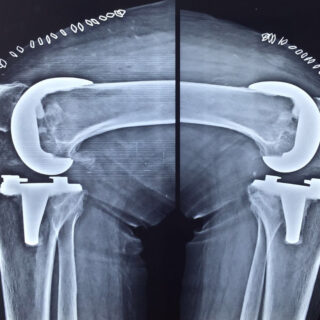

X-rays of patient of bilateral knee replacement in one sitting before and after surgery

Post Operation X-rays